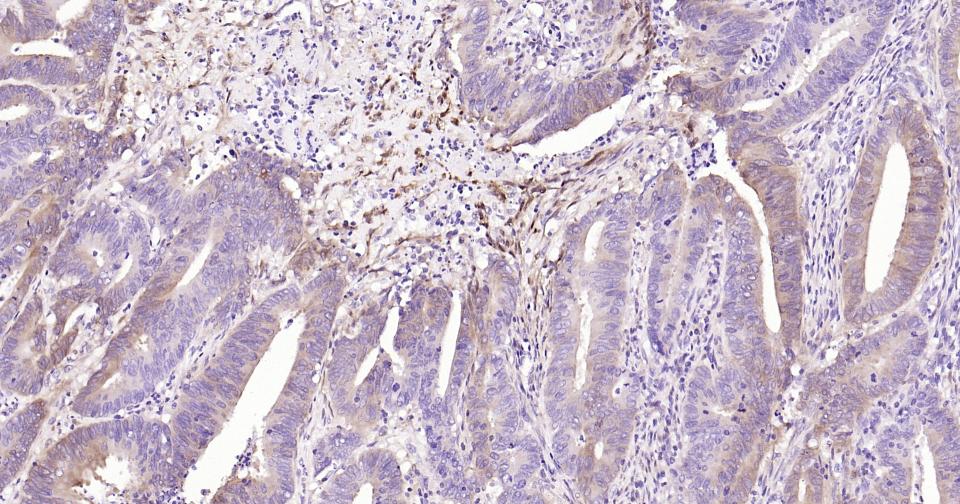

Paraformaldehyde-fixed, paraffin embedded Human Colon Cancer; Antigen retrieval by boiling in sodium citrate buffer (pH6.0) for 15 min; Antibody incubation with NSE Monoclonal Antibody, Unconjugated(bsm-60786R) at 1:200 overnight at 4°C, followed by conjugation to the SP Kit(Rabbit, SP-0023) and DAB (C-0010) staining.